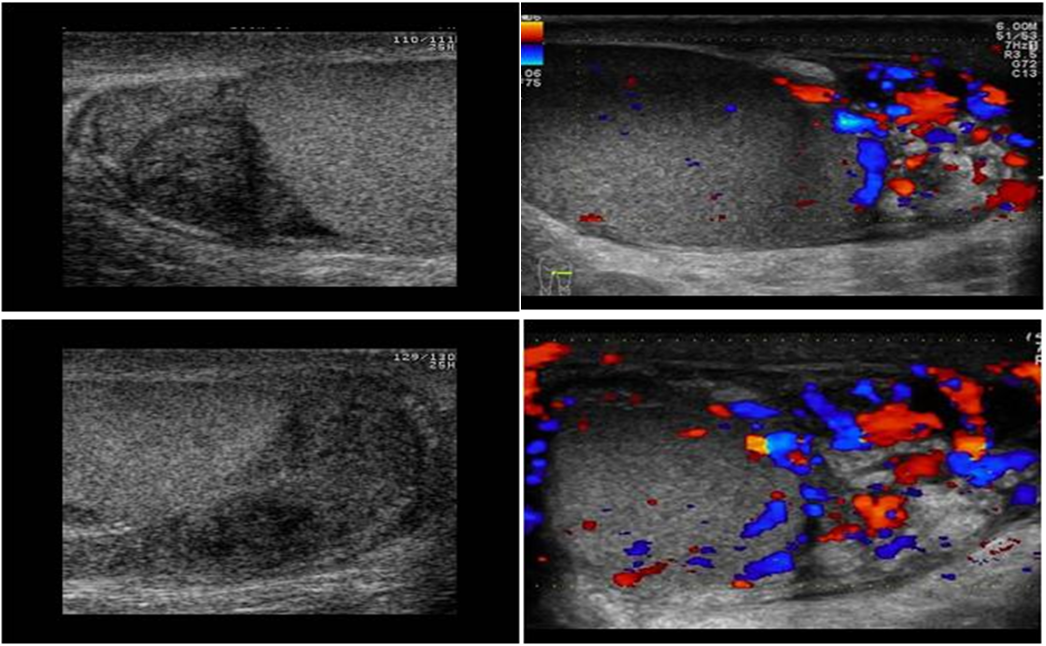

Ultrasound:

Reactive hydrocele and scrotal wall thickening , edematous epididymis and shows increase vascularity on Doppler